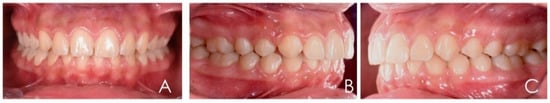

3.2. Clinical Case #2